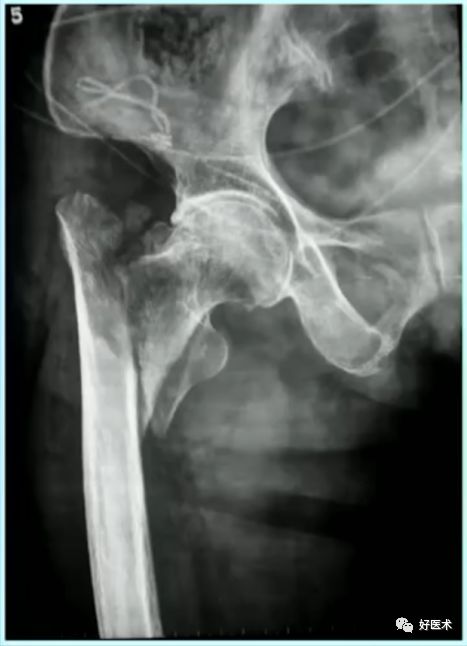

病例:男,34岁,高处坠落伤,仅骨折余正常

处理方法:

-

髓内钉(开放VS闭合)

钢板

其他

术前牵引